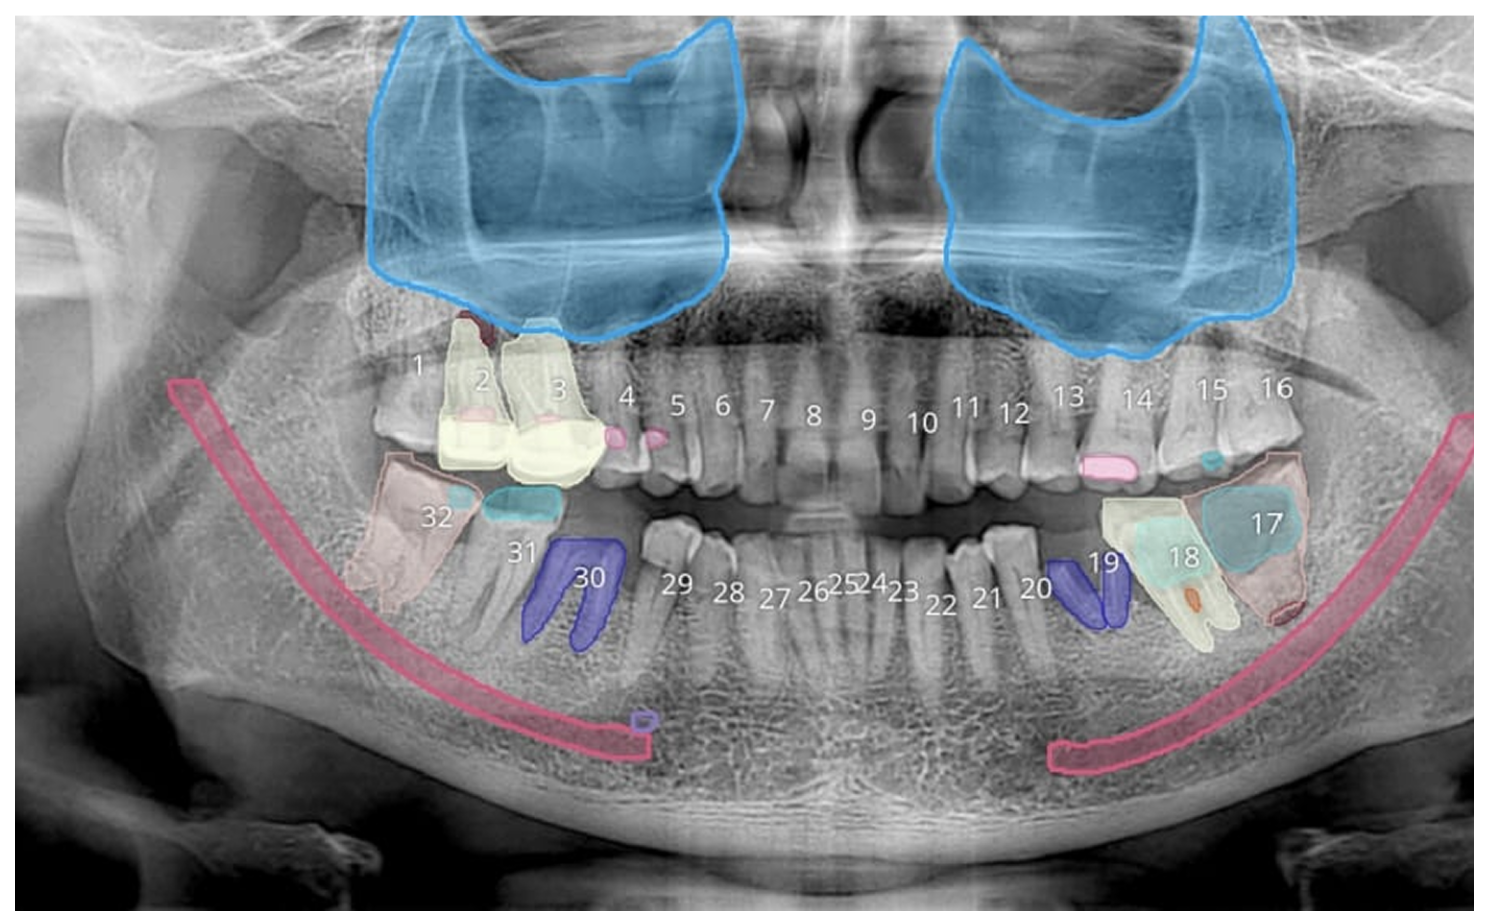

The future of dental imaging lies in combining CBCT with AI-driven analysis where high-quality 3D data is enhanced by intelligent tools to support faster, more consistent, and clinically relevant decision-making.

CBCT already gives dentists complete 3D visibility. But the next evolution is not just about seeing more, it’s about understanding faster and more consistently.

This is where AI comes in. Instead of replacing clinical expertise, AI works as: a decision-support layer on top of CBCT imaging.

Modern AI systems can:

This means: You move from manual interpretation → assisted analysis

But importantly:

AI does not replace radiologists or dentists

It supports their clinical judgment

At Nidaan Dental, AI is used as a structured support layer designed to assist radiologists and dentists in faster, more consistent interpretation, without replacing clinical judgment.

In OPG imaging, AI is applied at the screening and visualization level.

Here’s how it works in practice:

This allows:

You (as a dentist) to quickly identify areas that need attention

Faster initial case understanding before detailed review

But importantly: These markings are indicative, not diagnostic

They act as a visual aid, helping you focus not replacing your evaluation.